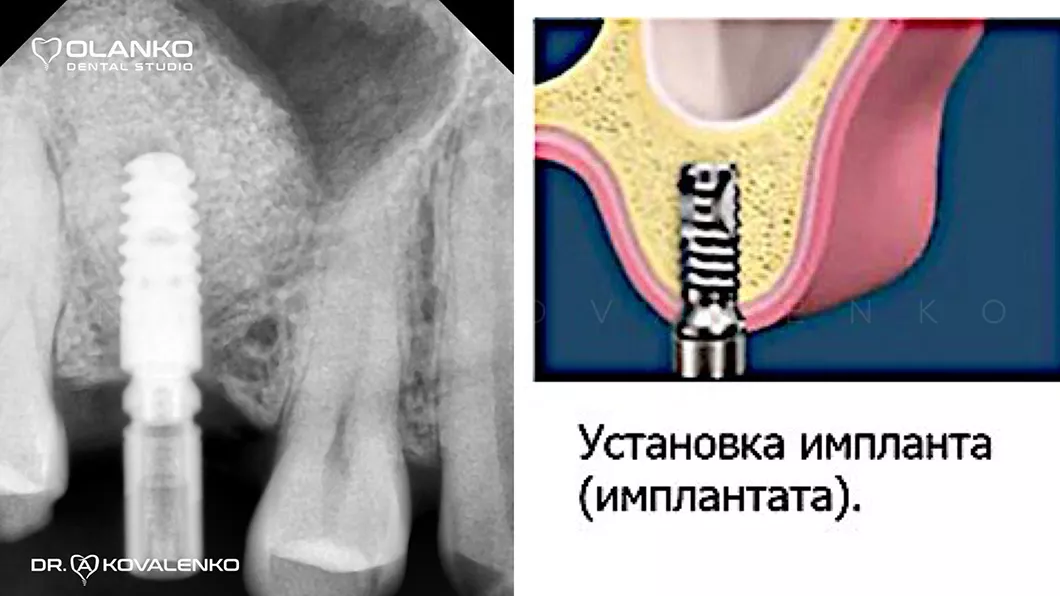

Операция костной пластики может выполнятся как самостоятельно, так и совместно с установкой зубного имплантата.

Специалисты Olanko dental studio (Оланко) г. Бровары, при выборе метода костной пластики, проводят детальный анализ компьютерной томографии и виртуально расставляют положение будущих имплантатов в специальном программном обеспечении IMPLANT STUDIO 3Shape.

Установка имплантата после наращивание костной ткани Оланко Бровары Киев